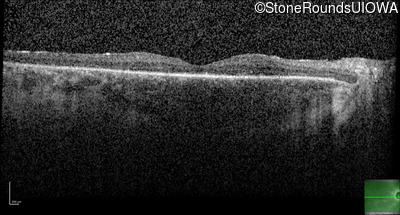

Optical Coherence Tomography - Right - 20/50

Exemplar / OCT Stack

OCT Stack